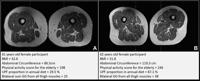

(University of California, San Francisco / Radiology via SWNS)

For the new research, published in the journal Radiology, American researchers set out to assess the relationship of UPF intake and intramuscular fat in the thigh.

Akkaya, from the University of California, San Francisco, explained that can be seen via MRI scans as fatty degeneration of the muscle, where streaks of fat replace muscle fibers.

She said: "In addition to investigating the quality of our modern diet in relationship to thigh muscle composition, in this study, we used widely available, non-enhanced MRI, making our approach accessible and practical for routine clinical use and future studies.

"These MRIs do not require advanced or costly technology, which means they can be easily incorporated into standard diagnostic practices."

"This is the first study assessing ultra-processed food's impact on thigh muscle composition using MRI."